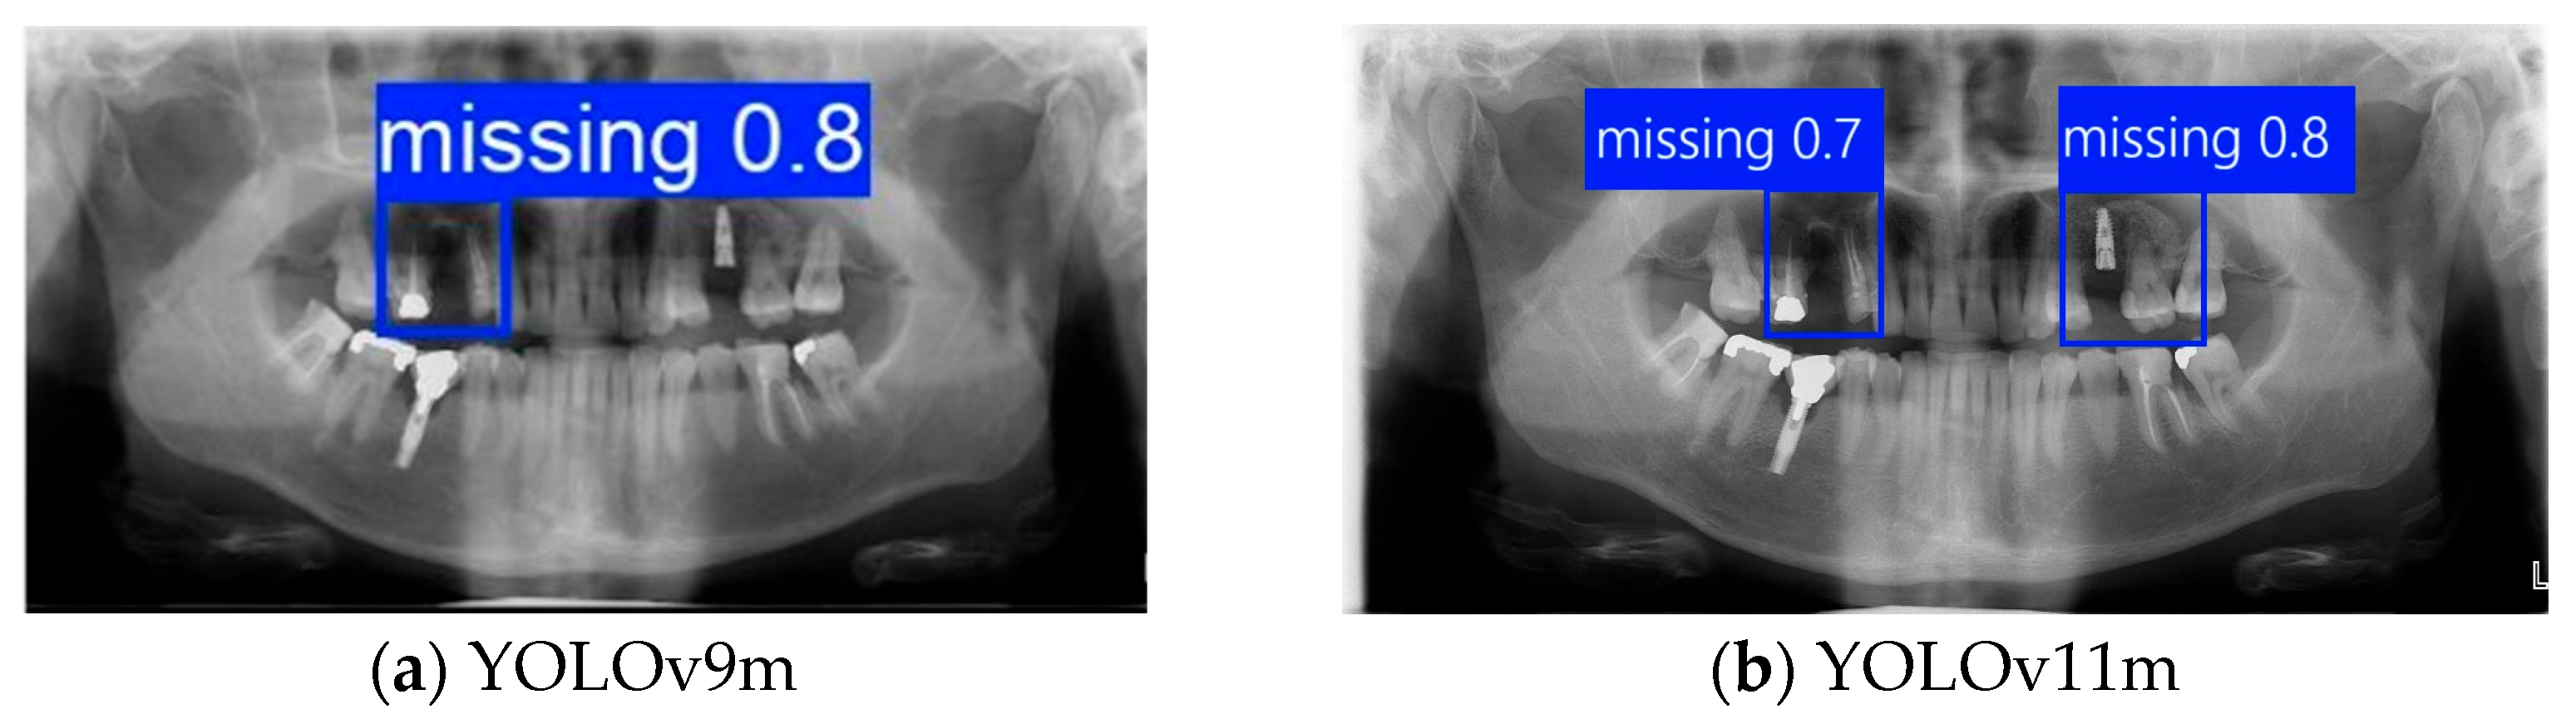

Further analysis revealed that although YOLOv11m performed slightly better on specific metrics, it was more prone to detection box shifts or overlaps in test images with complex backgrounds or blurred tooth boundaries, leading to reduced segmentation accuracy. As shown in Figure 10b, YOLOv11m produced detections with higher confidence scores; however, the predicted locations often deviated from the actual tooth positions. In contrast, Figure 10a illustrates that YOLOv9m, despite yielding slightly lower confidence scores, achieved superior localization accuracy with fewer false positives. This advantage was particularly evident in challenging cases involving blurred edges or narrow interdental spacing, where YOLOv9m consistently delivered stable predictions. The detection boxes generated by YOLOv9m provided higher accuracy and adhered more closely to the actual tooth contours, demonstrating greater stability and practical applicability. These strengths make YOLOv9m more suitable for subsequent fine-grained image segmentation and detailed dental structure analysis. Therefore, YOLOv9m was ultimately selected as the primary model for the following experiments, and all further applications and performance evaluations were conducted based on its outputs.

Figure 10.

Instance segmentation result comparison.